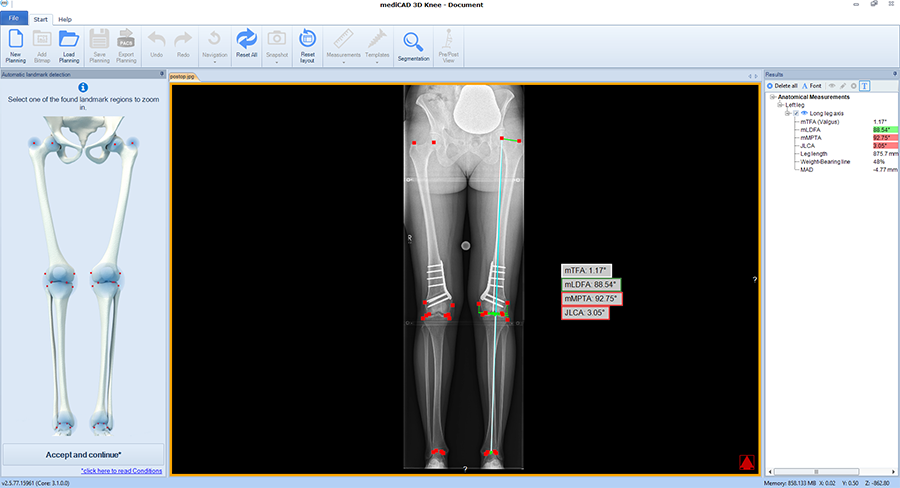

Next, deformity correction is visualized to the preferred new alignment. If a monofocal correction results in pathological joint angles, the implemented algorithm recommends double-level osteotomy and balance the two osteotomies between multiple constraints and normal values such as wedge heights, mechanical medial proximal tibial angle (mMPTA), mechanical lateral distal femoral angle (mLDFA), mechanical tibiofemoral angle (mTFA); (Fig 4).

Case 3

(Case provided by Steffen Schröter)

A 52-year-old man, a heavy worker was still able to work, however he was administered pain killers. During weekends only brief bike rides were tolerable. He reported an effusion and on that evening further daily activities were not possible. He complained of pain in the medial compartment. Excessive bowing legs were noticeable. Ligaments were stable in the sagittal plane but there was a medial instability in the coronal plane because of damage to the cartilage. He underwent double-level osteotomy for correction of the leg alignment.